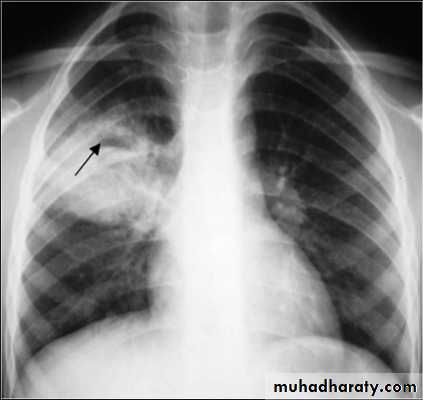

Fungus ball (air crescent sign)

Early rupture is sen as a cresnt air sign .ddx aspergillus ball